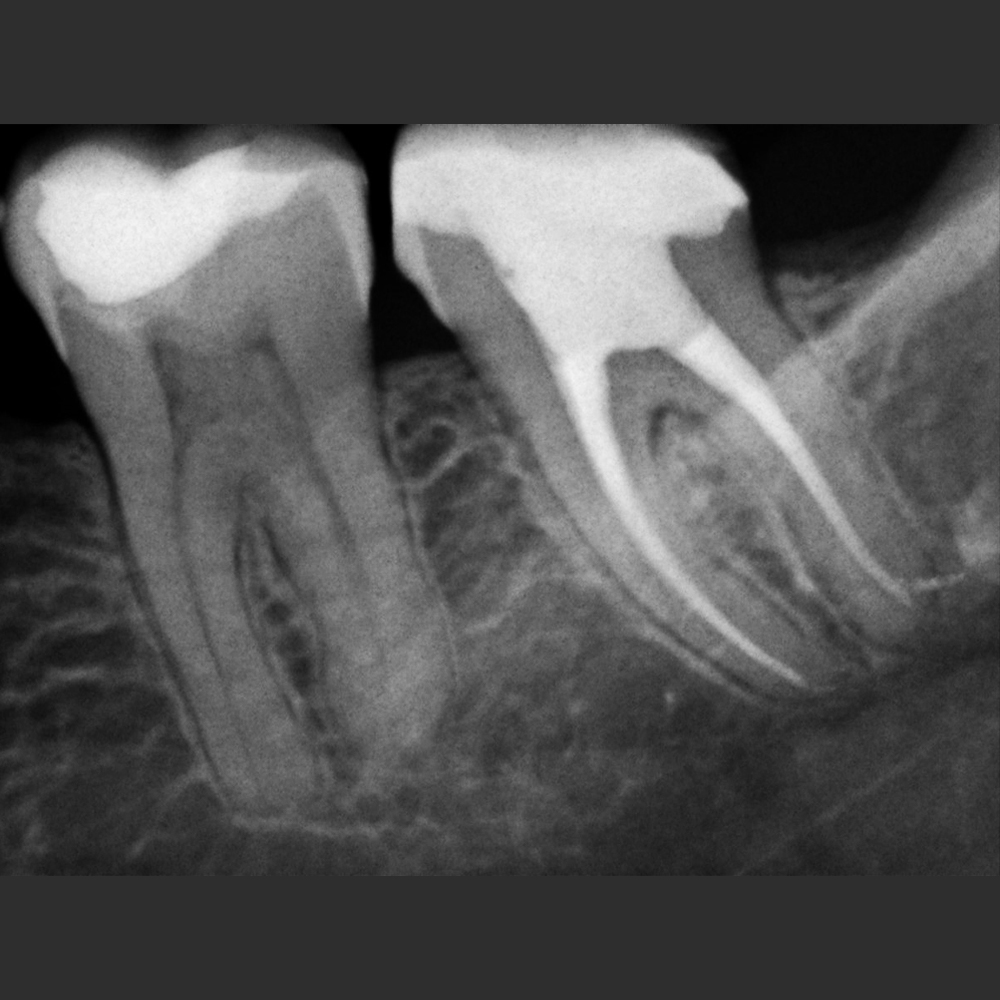

New IDA son los sensores intraorales de la linea New Ida con soluciones eficientes de las imágenes para un diagnóstico nítido, preciso y seguro.

Captura imágenes de alta definición en tiempo real.